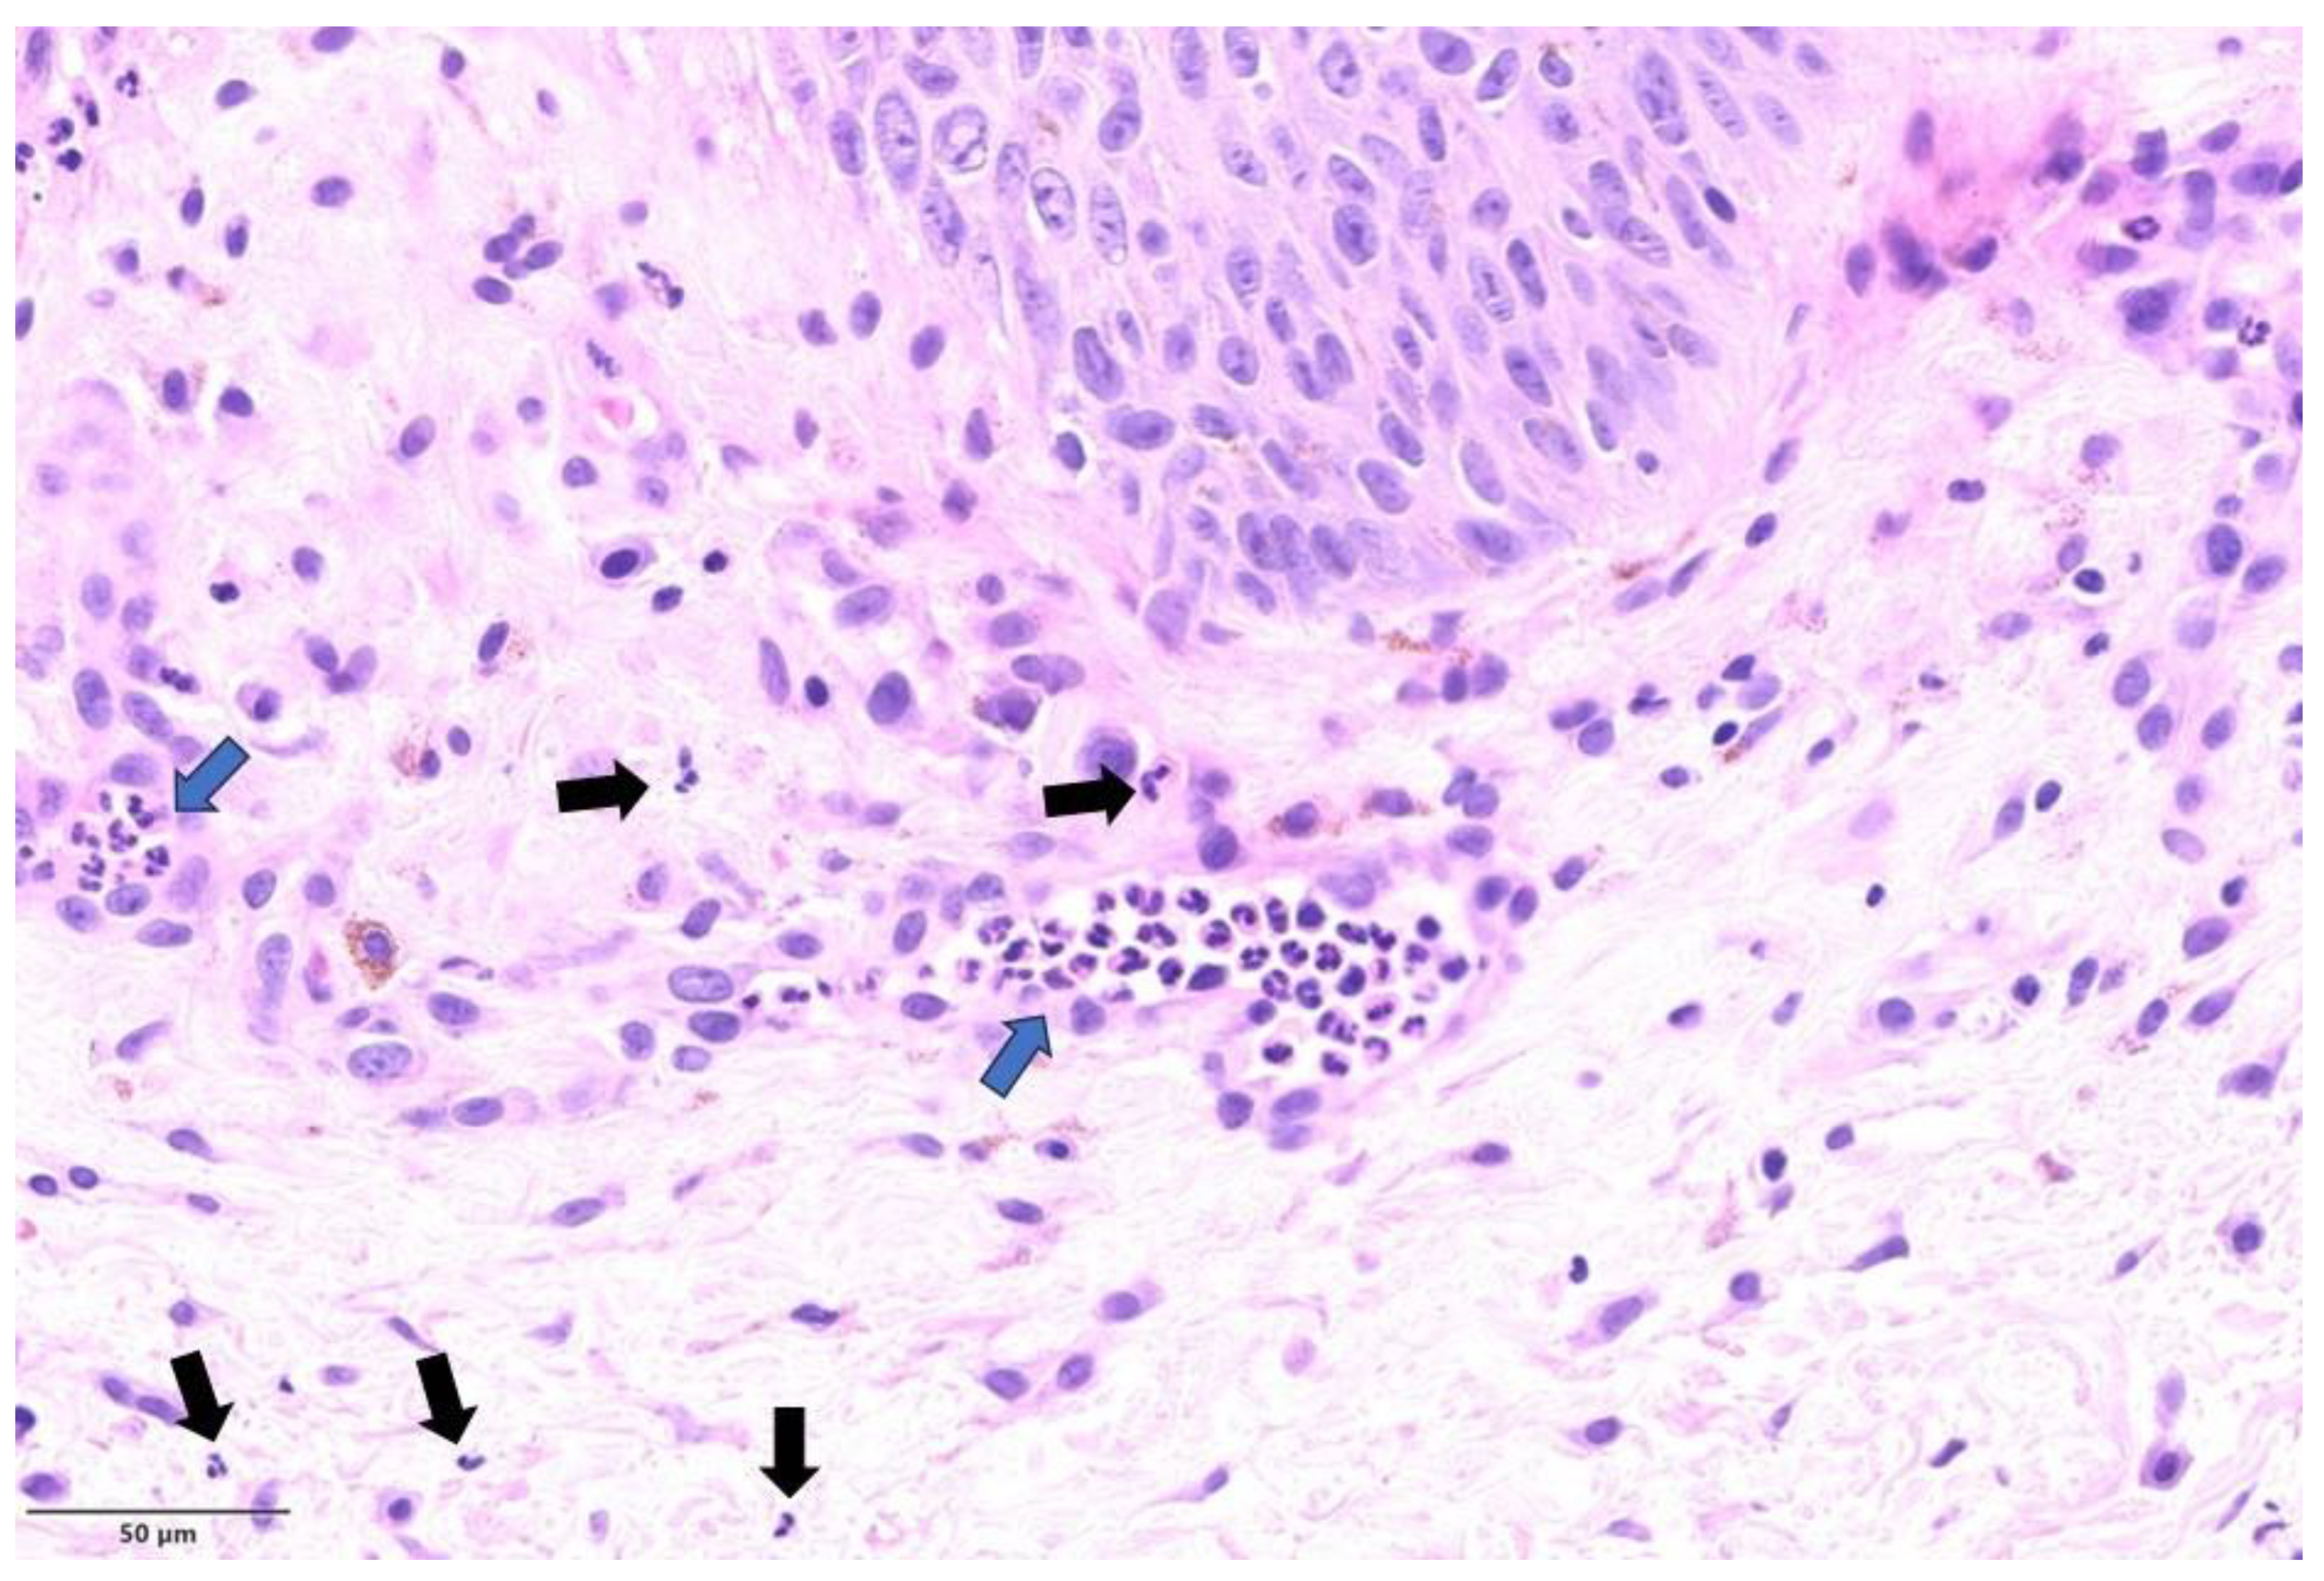

| 1 | Left thigh; penile shaft | Pustular stage | Multinucleated keratinocytes; occasional Guarnieri bodies; extensive ballooning; ground glass nuclei; degenerative modifications in the acrosyringial epithelium | Moderate perivascular and periadnexal with neutrophils |

| 2 | Penile | Pustular stage | Ground glass nuclei; ballooning; degenerative modifications in follicular keratinocytes | Mild perivascular lymphocytic infiltration |

| 3 | Groin, left shoulder | Pustular stage | Ballooning; occasional Guarnieri bodies; degenerative modifications in follicular keratinocytes | Moderate perivascular and periadnexal with neutrophils |

| 4 | Penile shaft | Pustular stage | Guarnieri bodies; ballooning; positive immunohistochemical staining for Treponema pallidum with spirochetes in cytoplasm of keratinocytes | Moderate perivascular and periadnexal with neutrophils |

| 5 | Pubic region | Vesicular stage | Ballooning; spongiosis and achantosis; degenerative modifications in the acrosyringial epithelium | Severe perivascular, interstitial, and periadnexal with neutrophils |

| 6 | Pubic region | Not applicable | Focal follicular dyskeratosis; positive immunohistochemical staining for Treponema pallidum with perivascular and intraepithelial spirochetes | Severe periadnexal and interstitial lymphocytic infiltration with numerous plasma cells |